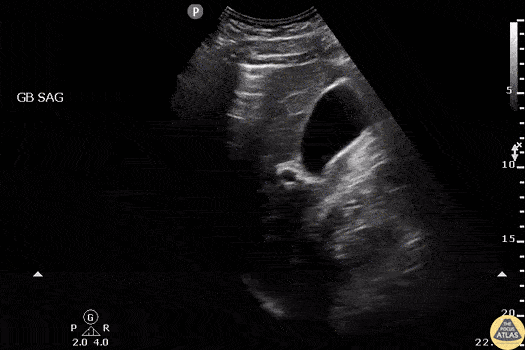

Patient presented with severe right upper quadrant abdominal pain. POCUS revealed pneumoperitoneum due to a perforated duodenum. The pneumoperitoneum can be identified as the A-line pattern seen superior to a portion of the liver consistent with air in the wrong place! Image courtesy of Robert Jones DO, FACEP @RJonesSonoEM Director, Emergency Ultrasound; MetroHealth Medical Center; Professor, Case Western Reserve Medical School, Cleveland, OH View his original post here